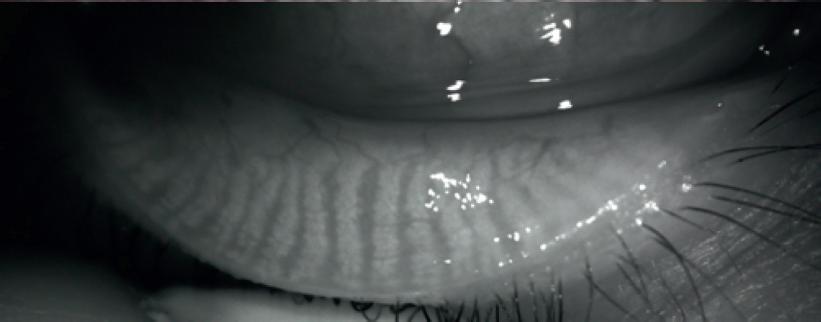

Tearcheck® (E-Swin,Houdan,France)isastand-alonedevicewithanintegrated screenthatallowstheusertoviewallacquisitionsandexamsinrealtime.Thedevice facilitatesquickevaluationsthatincludenineexaminations:non-invasivebreaktime,tear filmstability,ocularsurfaceinflammatoryassessment,meibographyIR,Demodex,eye redness,abortiveblinking,tearmeniscusheight,andtheOSDIquestionnaire.Thisresults inasimpledryeyeanalysis.

UsingtheDemodexexam,anenlargedimageofthebaseoftheeyelashescanbe obtained,allowingforthetracingandvisualizationofsignsindicatingthepresenceof Demodexmites.Asaresult,thedevicetakeshigh-resolutionimagesoftheocularsurface, enablingthedetectionofchangesinthecornea,conjunctiva,andtearfilm,suchasthe existenceofinflammationorocularsurfacedamage(dryspotsorerosion).